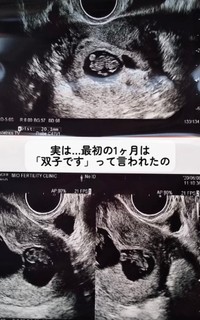

地元では珍しいコウノトリを発見!「願掛けで待ち受けにしたら」→1カ月後に三つ子が!……夫婦で感動「やっぱり奇跡だったんだね」